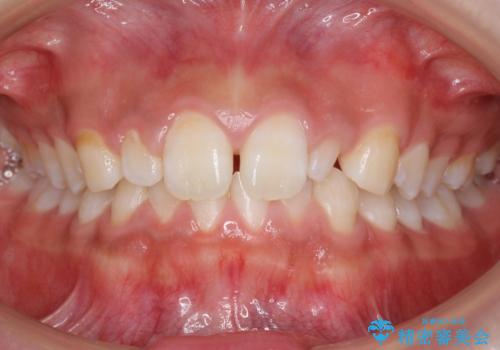

部分矯正+上の前歯のセラミック

- 部分矯正で下の歯1本が飛び出して上の歯に強く当たっている状態を解消してから、上の歯のかぶせもののやり直しを行いました。

矯正治療とセラミッククラウンを行うことで、上のセラミッククラウンも長持ちするような形で作成することができました。

気になっていた下の前歯の並びもきれいになり、患者様には大変満足していただきました。

一般的に歯のがたがたをそのまま並べると前歯は前方に出てしまいます。今回は、上のかぶせものに下の前歯が強くあたらないように、歯を少しやすりがけして(ディスキングといいます)なるべく内側に並べるようにしました。

部分矯正ですので、奥歯のかみ合わせは変わっていません。

ブラケットもわずかな本数(6本)のみで、4ヶ月と短期間ながら非常に有用な治療になったと思います。